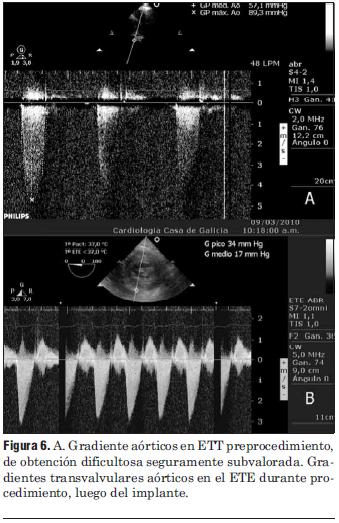

Dados los resultados de los estudios previos se entendió que el paciente era pasible de implante percutáneo de prótesis válvular aórtica autoexpandible CoreValve®. El 9 de marzo de 2010 se realizó el implante en el laboratorio de hemodinamia. Se realizó profilaxis con cefalosporinas. Previo al procedimiento se realizó anestesia general con IOT y ARM, colocación de sonda transesofágica de ecocardiograma, colocación de marcapaso transitorio en ventrículo derecho por vía subclavia izquierda, VVC y punción arterial femoral izquierda para introducción de catéter pigtail 6 F que sirvió para realizar aortograma, medir gradientes y controlar posicionamiento de prótesis valvular. Se colocó introductor arterial 18 F por punción femoral derecha y se realizó valvuloplastia aórtica con balón NUMED 25 x 4.0 mm con sobreestimulación simultánea a 180 cpm para evitar el desplazamiento del balón (figuras 2 y 3). A continuación se colocó la prótesis valvular aórtica CoreValve® Nº 29 a nivel del anillo valvular aórtico (figura 4). Se realizó control angiográfico y hemodinámico observándose mínima insuficiencia valvular aórtica y gradiente transvalvular de 30 mm (figura 5). Se cerró el orificio de punción arterial femoral derecha con Prostar XL®. El procedimiento se realizó con éxito clínico, angiográfico y hemodinámico. La figura 6 muestra los gradientes transvalvulares pre y postprocedimiento inmediato por ecocardiografía. Durante el mismo no hubo eventos ni complicaciones. En la evolución intrahospitalaria en CTI se constató sangrado en la zona de punción femoral derecha que requirió cierre definitivo con cirugía vascular. El 13 de marzo de 2010 se retiró el marcapaso transitorio, sin registrarse episodios de bloqueo auriculoventricular y es dado de alta de CTI a sala donde evoluciona estable. El 15 de marzo de 2010 se realizó ecocardiograma de control que mostró prótesis aórtica normofuncionante, gradiente máximo 20 mm Hg y medio 12 mm Hg y leve insuficiencia. El 16 de marzo de 2010 es dado de alta a domicilio en buenas condiciones. Se realizó control clínico a los 15 días permaneciendo estable bajo tratamiento con ácido acetilsalicílico, clopidogrel, betabloqueantes, trimetazidina y estatinas. A los 45 días del procedimiento el paciente permanece asintomático con igual tratamiento farmacológico y se controló con nuevo ecocardiograma que mostró: prótesis biológica en posición aórtica con sigmoideas normales, gradiente sistólico pico de 23 mmHg y medio de 13 mmHg, índice de obstrucción 0,43 y mínima insuficiencia perivalvular; leve hipertrofia ventricular izquierda con contractilidad global y segmentaria conservada.

Figura 6. A. Gradiente aórticos en ETT preprocedimiento, de obtención dificultosa seguramente subvalorada. Gradientes transvalvulares aórticos en el ETE durante procedimiento, luego del implante.